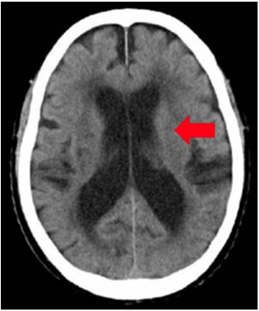

アルツハイマー病

VSRAD(ブイエスラド)

早期アルツハイマー型認知症診断支援システム

認知症を早期に画像で診断できます。